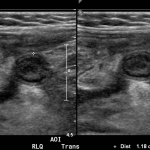

In the long axis video, the appendix appears as an enlarged, non-compressible, blind-ending tubular structure (white arrow) with distinct appendiceal wall layers and lack of peristalsis. In the short axis video, the appendix appears as a target sign (yellow arrow) between the abdominal and psoas muscles. The maximal outer diameter (MOD) measures 11.8mm and the appendix wall measures 0.17mm. There is trace adjacent free fluid and echogenic periappendiceal fat. Transverse axis video and image (red arrow) demonstrate that the appendix is not compressible. These findings are consistent with acute appendicitis.